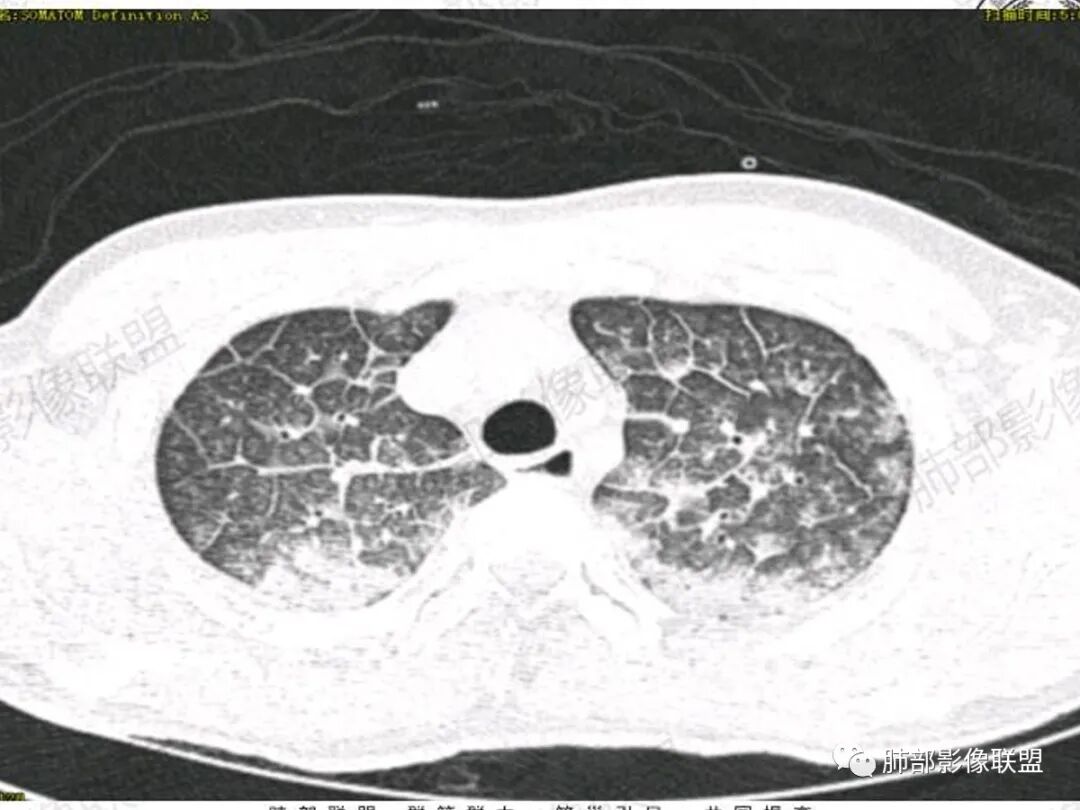

双肺上叶,下叶背段多发斑片状实变影,以胸膜下分布为主,部分重力作用,以背侧为主,部分小叶间质增厚,部分周围伴有散在磨玻璃影,边界欠清,临床急性病程,血象增及PCT明显增高,意识模糊,考虑:吸入性肺炎?鉴别:AHP?CEP?PCP

37岁男性 气促 两肺对称分布磨玻璃及小叶间隔增厚,两肺上叶后段及下叶背段为著,有重力分布,下部密度较高,请结合病史排查肺水肿,理化性肺泡损伤

双肺叶透亮度对称性减低,呈磨砂状,小叶间隔规则增厚,上叶为甚,左右肺叶中轴间质增厚(示淋巴回流障碍),双肺叶弥散磨GGO征,以肺腺泡分布,双肺上,下叶融合片状,有重力分布特点,心脏大,肺动脉干增粗,首选心源性肺水肿,但无胸腔积液。与急性肺损伤和ARDS鉴别

影像:两肺上叶小叶间隔增厚,斑片,腺泡结节,重力分布,下肺不累及

影像学提示肺水肿与肺泡腔液性渗出(小叶间隔增厚+实变+重力趋势),上叶显著。

青年男性,气促7小时入院,意识模糊,白细胞及中性粒明显增高,PCT增高,CRP不高,心率快,体温正常,血压正常。胸部CT:双肺上叶小叶间隔光滑增厚,中轴间质增厚,弥漫性磨玻璃、多发斑片影,以上肺、背侧分布为主。影像表现考虑为肺水肿。病因:病史不支持肾功能衰竭、心源性、高原性肺水肿,无发热,似乎也不支持细菌、病毒、真菌等感染引起。吸入毒物?吸入水?

对称性小叶间隔增厚

高密度影重力趋势

病灶的分布以上肺为主

确实要考虑吸入,倾向于吸入的是气体类的可能,因为朝上走

结合病史,最终诊断是 “急性烟雾吸入性肺损伤”,影像学表现主要是肺水肿及弥漫性肺泡损伤改变,因为烟雾气体吸入肺内分布以上肺显著,因此影像学表现也是累及上肺更明显。损伤因素包括大量一氧化碳 二氧化碳 一氧化氮等燃烧产生的有毒气体,也有烟雾粉尘颗粒对气道黏膜的损伤。